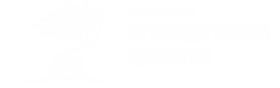

Пациентка 54 лет. Внешний вид и рентгенограмма в полный рост. Механическая ось смещена кнутри.

Основные осевые линии голени на рентгенограмме. В номе углы между этими линиями должны быть 85-90 градусов. Инородные тела в мягких тканях – остатки геля, введенного 30 лет назад.